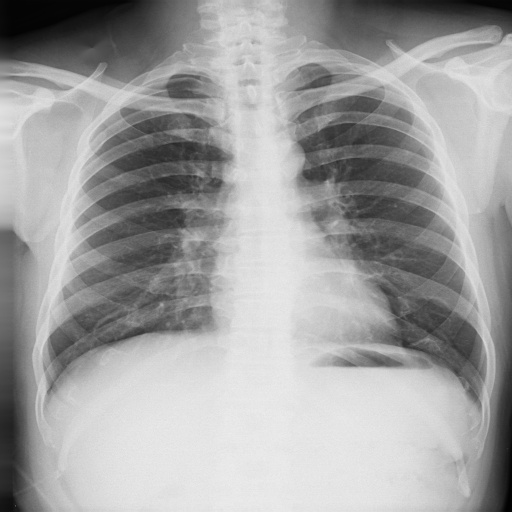

On the other hand, X-ray imaging is the most prevalent and data-intensive screening method in current medical image examinations. Chest X-ray (CXR) can swiftly detect lung abnormalities caused by pulmonary TB, making it a widely-used tool for TB screening. The World Health Organization also recommends CXR as the initial step in TB screening [13]. Early diagnosis through CXR significantly aids in early TB detection, treatment, and prevention of the disease’s spread [13, 14, 15, 5, 10]. However, even experienced radiologists may fail to identify TB infections in CXR images, as the human eye struggles to discern TB areas in CXR images due to its limited sensitivity to many details. Our human study reveals that experienced radiologists from top hospitals achieve an accuracy of only 68.7% when compared with the gold standard.

All CXR images are in a resolution of approximately . Each CXR image is accompanied by corresponding age and gender information, providing comprehensive clinical clues for the diagnosis of TB. The age distribution and gender distribution are presented in Fig. 1 and Fig. 2, respectively. From Fig. 1, it is evident that 60% of the TB patients fall within the age range of 20 to 60 years. Only a small percentage of young individuals (aged less than 20) are infected with TB, specifically 3% of TB patients. This finding is consistent with recent medical research [56, 57, 58]. Fig. 2 illustrates that the majority of TB patients are male, aligning with clinical observations that TB is more prevalent in men than women globally [59, 60]. We have annotated TB infection areas using bounding boxes (introduced in 3.1.3), and the distribution of the sizes of these TB bounding boxes is depicted in Fig. 3. As evident from the figure, TB infection areas exhibit a wide range of sizes, manifesting varying degrees of TB severity. Taken together with the previous analyses on taxonomy, category distribution, age distribution, gender distribution, and TB infection size distribution, we can come to the conclusion that the new TBX11K dataset is both representative of the general population and consistent with real-world clinical scenarios.

The radiologist achieves an accuracy of only 68.7% when compared to the ground truth produced by the golden standard. If we ignore the differentiation between active and latent TB, the accuracy improves to 84.8%, but distinguishing between the types of TB is crucial for effective clinical treatment. This low performance highlights one of the major challenges in TB diagnosis, treatment, and prevention. Unlike natural color images, CXR images are grayscale and often have fuzzy and blurry patterns, making accurate recognition challenging. Unfortunately, diagnosing TB with the golden standard can take several months in a BSL-3 laboratory [11, 12], which is not feasible in many parts of the world. The challenge in TB diagnosis leads to TB becoming the second most common infectious disease worldwide after HIV. However, we will show in our upcoming study that deep-learning-based CTD models trained on the proposed TBX11K dataset can significantly outperform even experienced radiologists, offering hope for improved TB diagnosis and treatment.